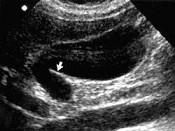

患者男,32岁,健康体检,提示?(?)A.双房胆囊B.皱折胆囊C.双胆囊D.胆囊憩室E.以上都不是

问题 患者男,32岁,健康体检,提示?(?)

选项 A.双房胆囊 B.皱折胆囊 C.双胆囊 D.胆囊憩室 E.以上都不是

答案 B